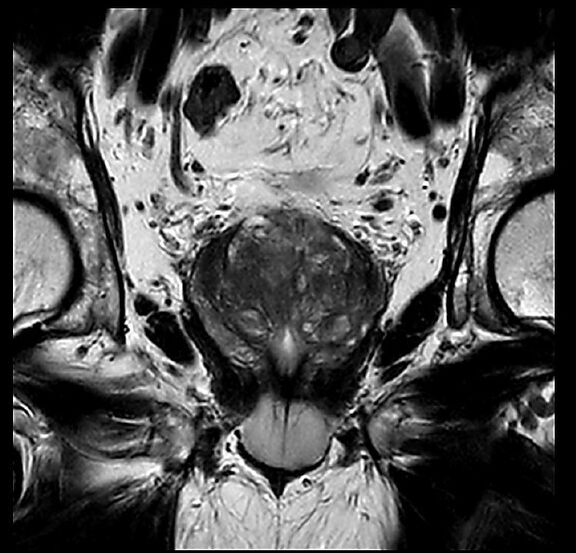

Beispiele von MRT-Prostata Aufnahmen